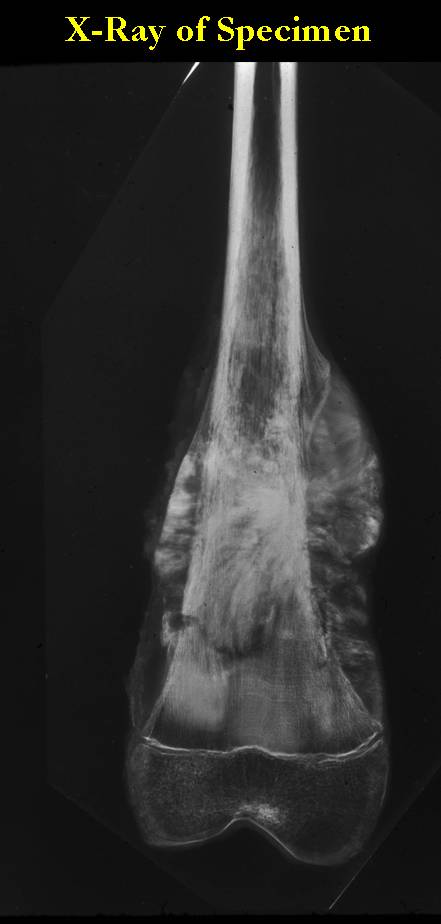

These are examples of the gross pathology specimens of resected conventional osteosarcoma, consisting of both bony and soft tissue areas. X-rays of the specimens are included.

- Osteosarcomas are composed of ossified or non-ossified tissue

- Ossified tissue is yellow-white and hard

- Less ossified tissue is soft and less yellow

- Non-ossified tissue is tan and fleshy

- Most (95%) of conventional osteosarcomas penetrate the cortex and form a large extraosseous soft tissue mass

- The lesion permeates the marrow spaces

- Osteosarcomas usually infiltrate the marrow several centimeters away from the main tumor mass

- Skip lesions may be apparent that are separated from the main tumor by normal marrow

- Osteosarcomas may also have cartilaginous components that appear as translucent lobules, and/or fibrous components that are tan, soft to firm rubbery areas

- Osteoblastic areas are usually white to yellow, firm, hard and gritty

- The consistency of the tumor depends on the amount of osteoid deposition, cartilaginous and fibrous areas

- Foci of hemorrhage and necrosis are common

- Periosteal reactions such as the Codman’s triangle are apparent at periphery of soft tissue mass

- Osteosarcomas rarely penetrate the growth plate grossly

- Invasion of the joint is uncommon but can occur by cortical penetration, joint capsule extension, or extension along cruciate ligaments